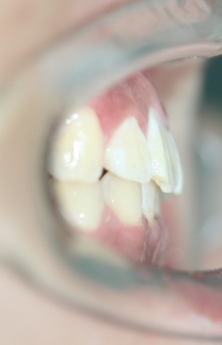

侧面观: 双唇前突 鼻唇角偏小 颏唇沟较深

左右侧磨牙均为一类咬合关系,前牙深覆合、深覆盖。

临床 前牙深覆合,深覆盖,后牙中性关系

上下前牙唇倾

双唇前突

3排齐排平,内收上下前牙,改善上下颌前倾和前突面型,协调上下颌咬合,保持!